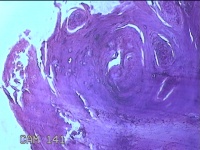

右侧拇指皮下结节

性别

男

年龄

40岁

临床诊断

皮下结节

一般病史

发现右侧拇指皮下结节1年余,无明显疼痛及不适。

标本名称

大体所见

灰白暗红色带皮肤结节0.8x0.3x0.2cm一个,表面糜烂,切开结节呈实性,切面灰白粉红色,质中。

图2